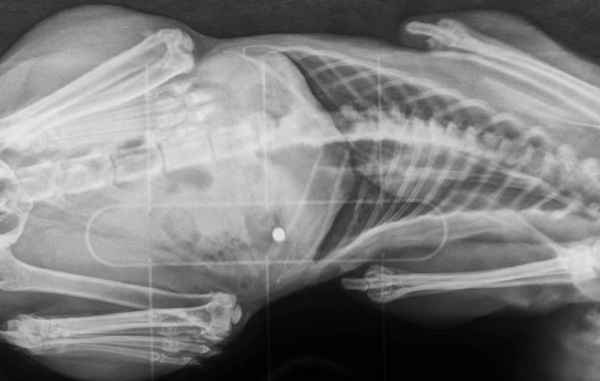

"Witam wszystkich posiadaczy i nie posiadaczy zwierzęcych przyjaciół. Pisze, aby ostrzec Was przed człowiekiem, który z przyczyn, których pojąć nie potrafię, strzela do bezbronnych zwierząt. Wczoraj tj. 27.04, zauważyłam, że moja kotka dziwnie się zachowuje, wygląda jakoś "nieswojo", widać było po niej również, że chodzenie jak i siedzenie sprawia jej trudność oraz ból. Na ciele znalazłam ranę, początkowo przypuszczałam, że to efekt walk terytorialnych z innymi kotami, atak jakiegoś psa lub niefortunne zahaczenie się jej o coś, przykładowo siatkę ogrodzeniową. Po wizycie u lekarza weterynarii, który stwierdził, że rana jest dokładnie jak po postrzale z.......WIATRÓWKI (!!!), zdjęcia RTG tylko to potwierdziły.